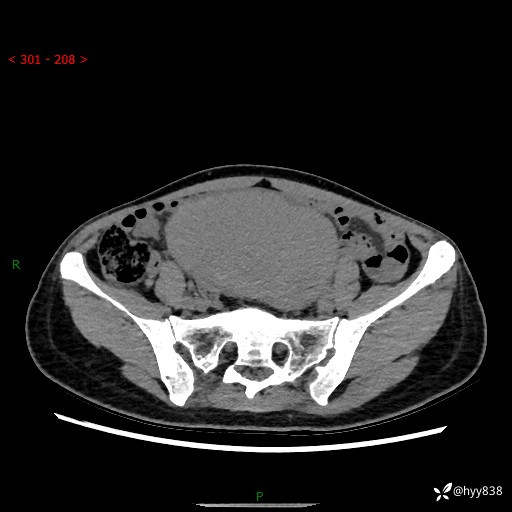

【患者信息】:女,50岁

【主诉】:外院超声发现腹盆肿块,为进一步诊治来我院,门诊已“盆腔肿块”收入院。

腹盆CT平扫+增强

【临床诊断】:盆腔肿瘤